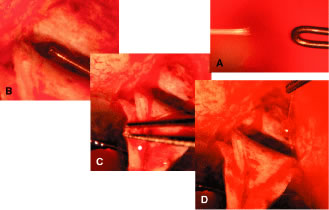

irrigated away, and chamber deepening cannot readily be performed.  Fig. 10. Peripheral iridectomy with the use of a preplaced suture to retract the

edges of the incision. A. An incision is made through two thirds of the thickness of the sclera

directly at the corneoscleral sulcus. B. A 9-0 white virgin silk suture is placed so that it will be able to be

retracted from the depths of the incision. C. The suture is looped and used to retract the edges of the incision superiorly

and inferiorly. The incision is completed, permitting prolapse

of a small knuckle of iris. D. The iris is grasped with a fine-toothed forceps. E. The iris is pulled over the blade of the DeWecker scissors; after the

position of the iris is noted, the blades are closed and the tissue is

excised. F. The tip of an irrigator is placed just inside the incision, with care

taken to ensure that it does not enter the anterior chamber. Remnants

of the pigment epithelium are flushed away, and the iris is permitted

to return to its proper position so that the pupil is completely round. (Spaeth GL. Glaucoma surgery. In Spaeth GL (ed). Ophthalmic Surgery: Principles

and Practice. Philadelphia: WB Saunders, 1990.) Fig. 10. Peripheral iridectomy with the use of a preplaced suture to retract the

edges of the incision. A. An incision is made through two thirds of the thickness of the sclera

directly at the corneoscleral sulcus. B. A 9-0 white virgin silk suture is placed so that it will be able to be

retracted from the depths of the incision. C. The suture is looped and used to retract the edges of the incision superiorly

and inferiorly. The incision is completed, permitting prolapse

of a small knuckle of iris. D. The iris is grasped with a fine-toothed forceps. E. The iris is pulled over the blade of the DeWecker scissors; after the

position of the iris is noted, the blades are closed and the tissue is

excised. F. The tip of an irrigator is placed just inside the incision, with care

taken to ensure that it does not enter the anterior chamber. Remnants

of the pigment epithelium are flushed away, and the iris is permitted

to return to its proper position so that the pupil is completely round. (Spaeth GL. Glaucoma surgery. In Spaeth GL (ed). Ophthalmic Surgery: Principles

and Practice. Philadelphia: WB Saunders, 1990.)